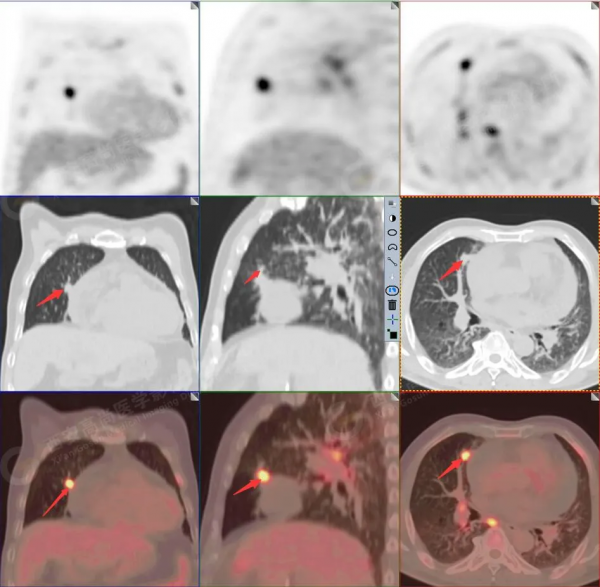

1.以下為肺內原發灶

1.右肺中葉內側段軟組織結節,呈淺分葉狀,邊緣可見毛刺及胸膜牽拉徵,呈FDG代謝異常增高,考慮為周圍型肺癌。

2.雙肺內瀰漫性分佈大小不等實性小結節灶及粟粒狀高密度影,均未見FDG代謝明顯異常增高,均多考慮為癌性淋巴結炎及轉移性病變。

3.右側頸部(Ⅱ-Ⅴ區)、右側腋窩區、右側肺門及縱隔(1R、1L、2、4、6、7組)、肝門區多發腫大淋巴結,呈不同程度異常增高,均考慮為淋巴結轉移。

4.肝S4、8段團塊狀及結節狀低密度病變,以S4段病變為著,呈不同程度FDG代謝異常增高,考慮為肝多發轉移。

5.右側肱骨上段、左側肩胛骨、右側鎖骨胸骨端、胸骨、雙側多發肋骨、脊柱多發椎體及附件、雙側髂骨、雙側髖臼、雙側恥骨、雙側肱骨上段多發成骨性病變,呈不同程度FDG代謝異常增高,考慮為多發骨轉移瘤。

以上病變符合:T4N3M1c,ⅣB期(UICC/AJCC,2018年第8版肺癌TNM分期)。